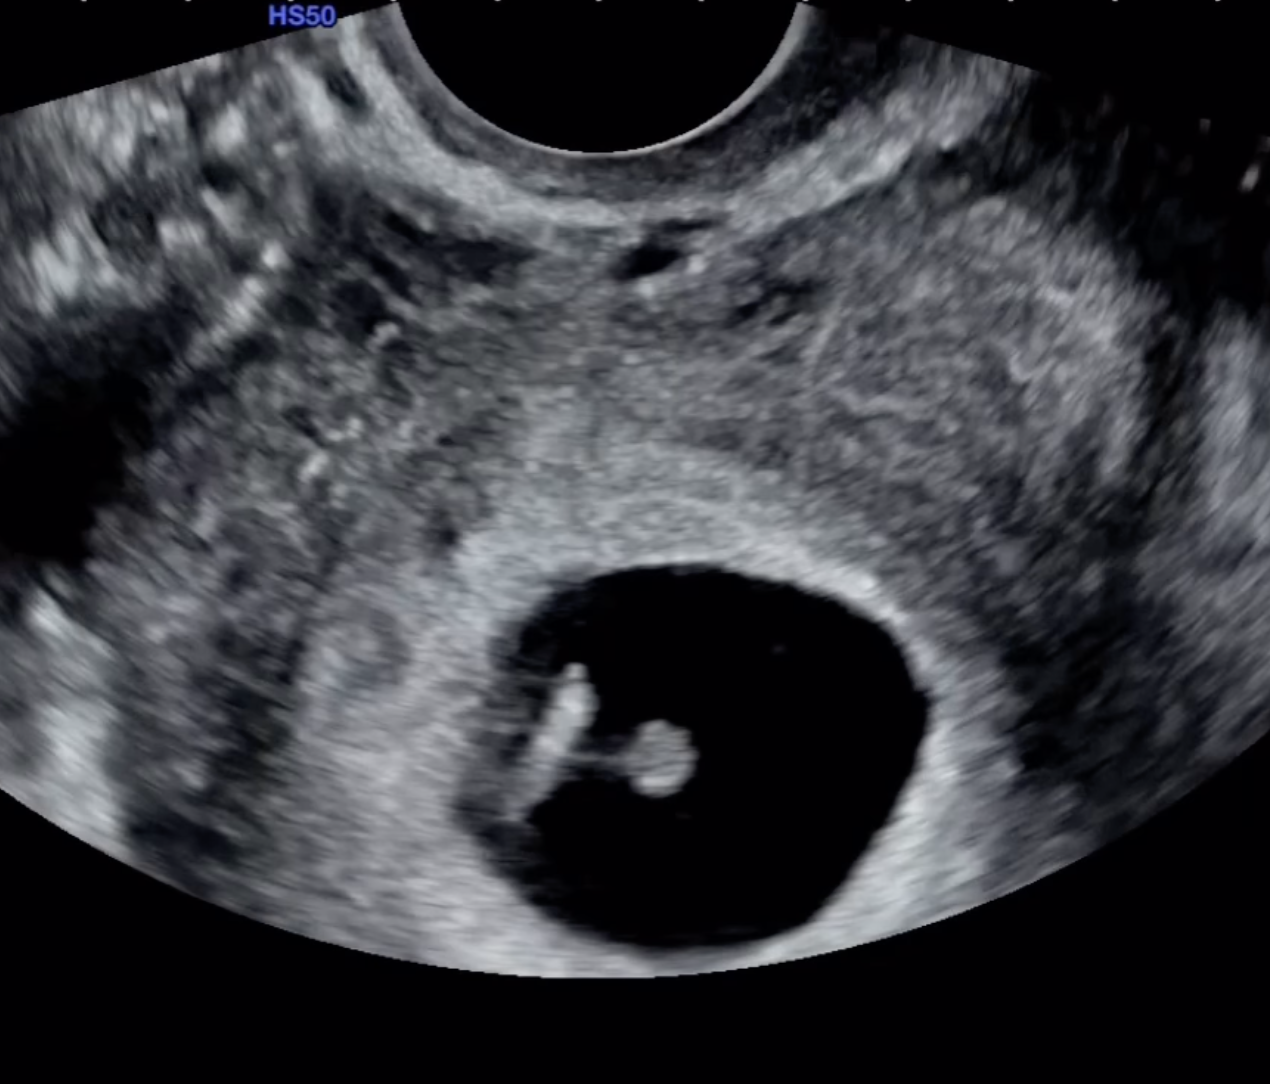

옥순 씨는 자신의 인스타그램 계정을 통해 초음파 사진을 공개하며 직접 임신 사실을 밝혔습니다.